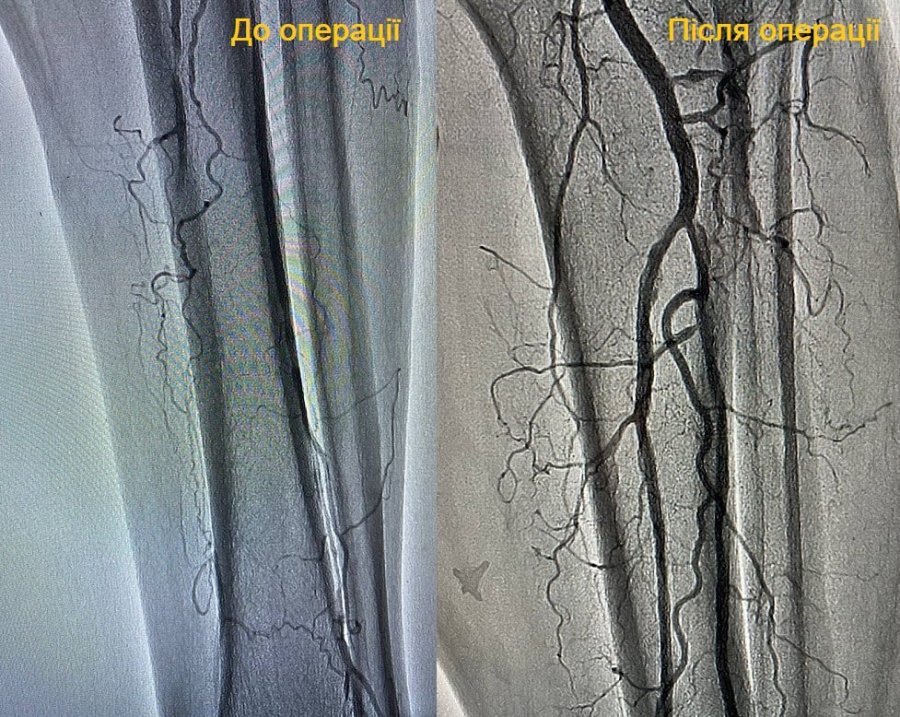

Так, днями виписали з лікарні 59-річного пацієнта-курця, який поступив з болями в лівій нозі, що посилювалися при ходьбі. Крім того, у нього почорнів перший палець стопи. Йому діагностували атеросклероз обох нижніх кінцівок.

Лікарі провели чоловікові балонну ангіопластику (роздуття) гомілкових артерій і стентування задньої великогомілкової артерії.

На щастя, чоловік вчасно звернувся за медичною допомогою і лікарі врятували йому ноги, відновивши порушене кровопостачання ендоваскулярним методом.